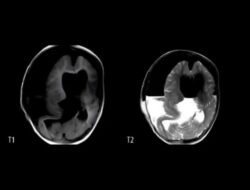

Kasus Langka! Janin Kembaran Terperangkap di Kepala Anak Usia 1 Tahun

loading… Seorang anak berusia 1 tahun ditemukan memiliki janin kembarannya yang terperangkap di dalam kepalanya….